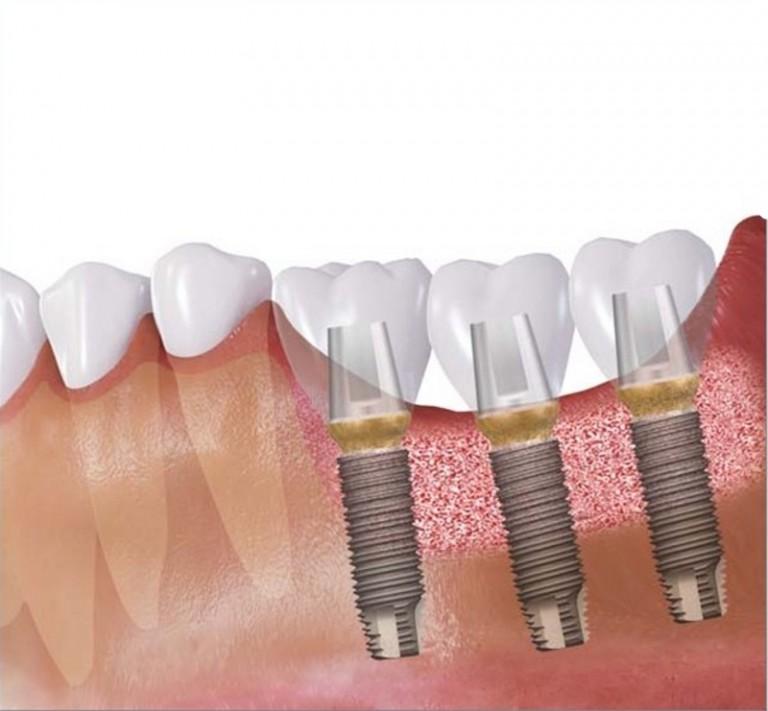

Sterowana regeneracja kości (GBR, Guided Bone Regeneration) wykorzystywana jest do odbudowy kości wyrostka zębodołowego w pożądanym wymiarze. Zabieg można wykonać podczas implantacji lub przed wprowadzeniem implantu, jako oddzielną procedurę. Uzyskuje się dzięki niemu poszerzenie lub podwyższenie wyrostka zębodołowego.

W implantologii regeneracji poddaje się kość wyrostka zębodołowego szczęki lub żuchwy, która uległa z różnych przyczyn zanikowi – jej niedostateczna ilość i jakość uniemożliwia wprowadzenie implantów. Po zakończeniu procesu sterowanej regeneracji, kość jest trwale zmieniona i często nie do odróżnienia od kości własnej.